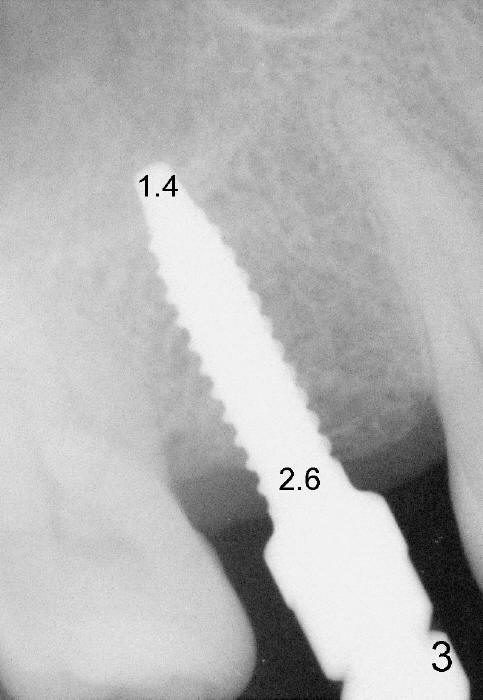

The 42-year-old lady is a dental phobic. The tooth #3 (residual root) is extracted 3.5 years ago. Finally she returns for implant (Fig.1). The mesiodistal space allows to place a 5x14 mm implant (Fig.2). Bone density is felt low when a 1.6 mm pilot drill is used. Bone condensation proceeds with bone expanders 2.6 mm (Fig.3) to 3.8 mm (Fig.4) 12 mm deep. Bone density is felt to increase with each larger expanders. When a 4x11 mm implant is placed (Fig.5), the insertion torque is 15 Ncm. When the diameter and length of the implant increase (Fig.6), the insertion torque is >60 Ncm. To have primary stability, the implant should be two sizes larger than the last expander (compare Fig.4,6)! In addition, the majority portion of the expanders is cylindrical (Fig.3,4), whereas the implant is tapered (Fig.5,6).

Another drawback of the implant placement is that the trajectory is off and distal (Fig.3-6), probably due to the low bone density in the distal aspect of the socket prior to extraction (Fig.7 CT sagittal section; MB: mesiobuccal root). The pilot drill must inadvertently have drifted distally and to the less dense bone (Fig.8). If it had been found, it could have been corrected early (Fig.9 red arrow). The trajectory could have been corrected immediately after the 2.6 mm expander (Fig.10). Ideally the pilot drill (Fig.11arrow) should be placed slightly mesial to the presumably mid edentulous line (red line) and only half of the length. If the trajectory is right, continue osteotomy (Fig.12). If not, correct it immediately.